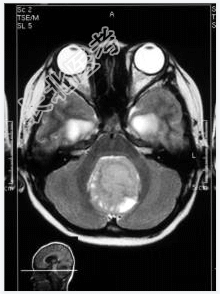

- [材料题] 患者,男性,10岁,因头晕、头疼伴呕吐1月,加重2天入院。做头颅MRI检查。

- 简答题1、诊断及依据是什么?

- 简答题2、鉴别诊断有哪些?